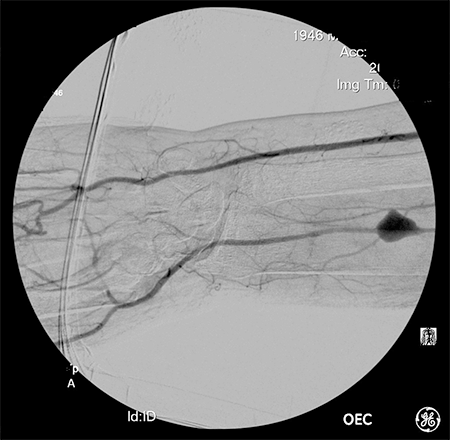

The patient was transferred to our regional hospital with severe sepsis and bacteremia. The source was identified as a severe soft tissue infection of the left forearm and associated mycotic aneurysm of the radial artery. On physical exam he was neurologically intact with palpable ulnar and radial pulses and excellent perfusion of the hand with modified Allen test. The forearm was red, warm, tensely swollen and exquisitely tender to palpation. The patient was taken to surgery urgently for forearm exploration and debridement. The operation commenced with 4 French left brachial artery access for intraoperative angiography. Imaging revealed a radial artery aneurysm, dominant ulnar artery, and complete superficial and deep palmar arches with normal digital arteries (Figure 4).

Figure 4. Intraoperative angiogram showing radial artery mycotic aneurysm. This is a true aneurysm as opposed to a more commonly seen pseudoaneurysm.